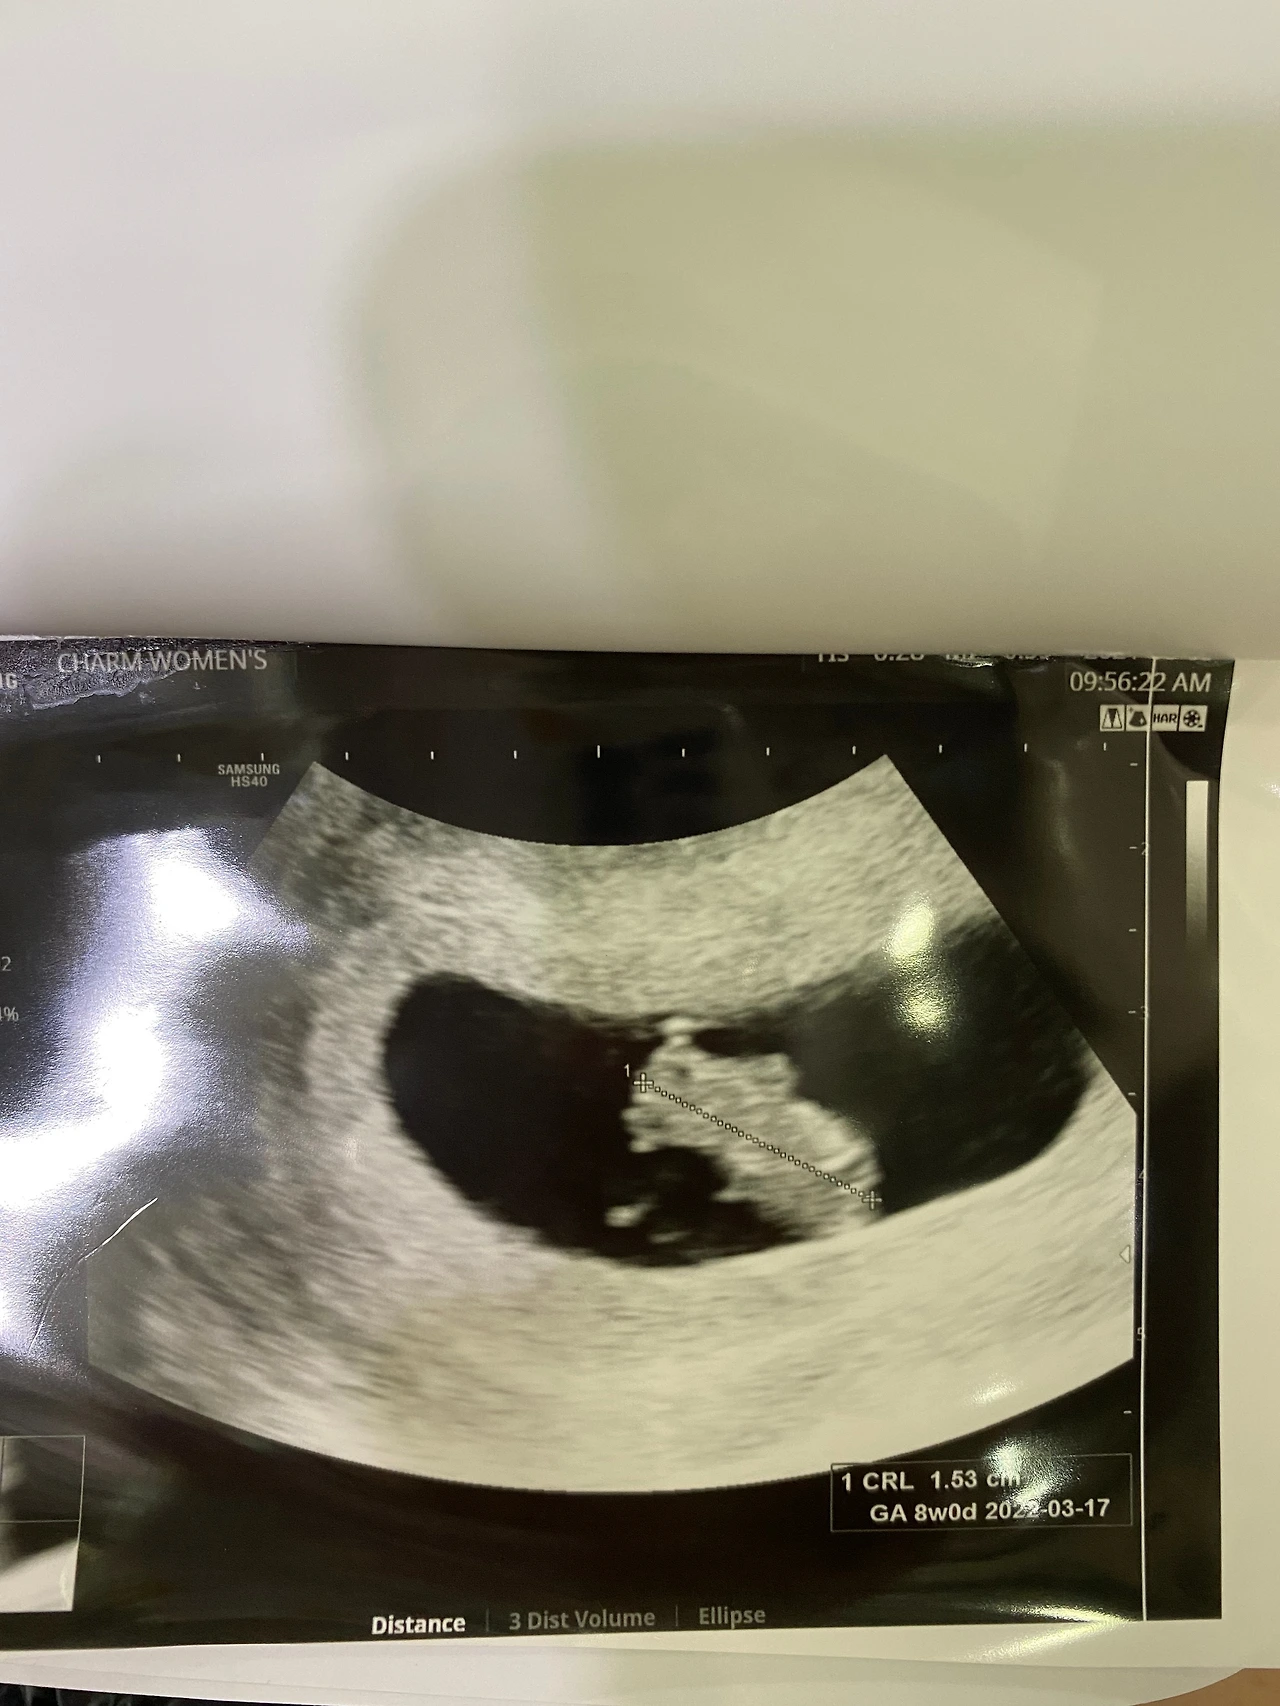

우리 동생이 둘째를 가졌다는 소식이 들렸다

첫째가 올해 7살인데 조금 뒤늦게 생긴 둘째

아빠가 점지해주시고 가셨는가보다며

그렇게 생각할 수 밖에 없다고 말하는 동생..